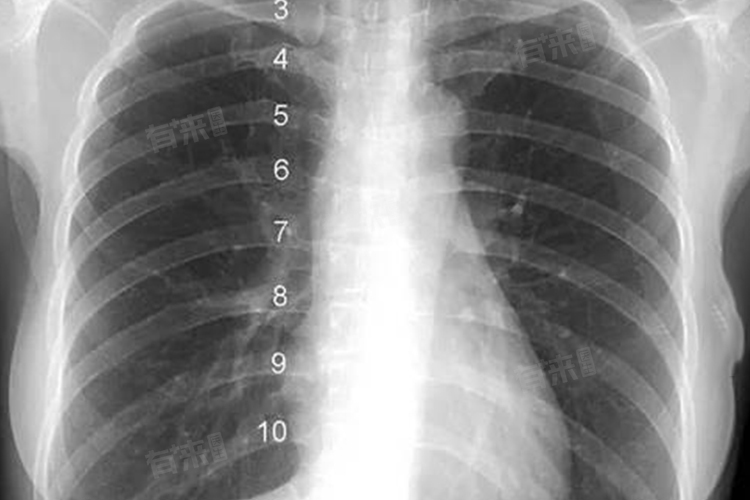

双侧肋膈角锐利在影像学检查中表现为肋膈角形态正常,没有明显异常。这一术语主要用于描述胸腔与腹腔交界处的肋膈角在X线或CT等影像学检查中的表现,肋膈角锐利通常意味着两侧的膈肌附着点较为靠上,且胸膜下脂肪组织较少,属于正常的解剖结构。但双侧肋膈角锐利也可能与疾病相关,如胸膜增厚或粘连、胸膜积液等。

- 双侧肋膈角锐利,这一医学影像学术语,通常出现在胸部X光或CT检查的报告中。表明胸腔内无积液,胸膜未增厚,是胸膜和胸膜腔处于正常状态的象征。